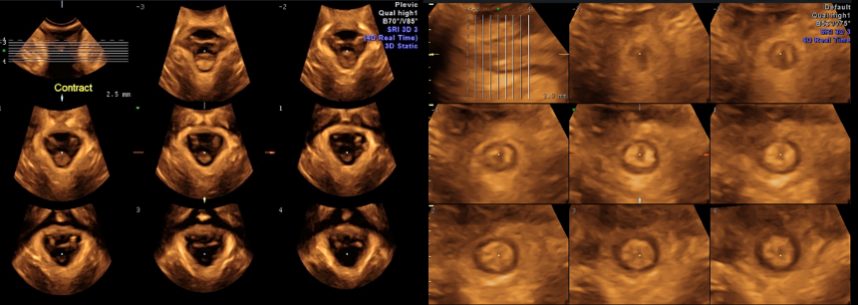

目前科室開展的三維/四維盆底超聲檢查可對盆底肌有無撕裂以及撕裂的范圍和程度、盆腔臟器有無脫垂以及脫垂的范圍和程度進行可視化評估,它是一雙雪亮的眼睛,能及時、科學的告訴您是否患病以及患病程度。

三維/四維超聲斷層成像觀察盆底肌(左圖恥骨直腸肌、右圖肛門括約肌)